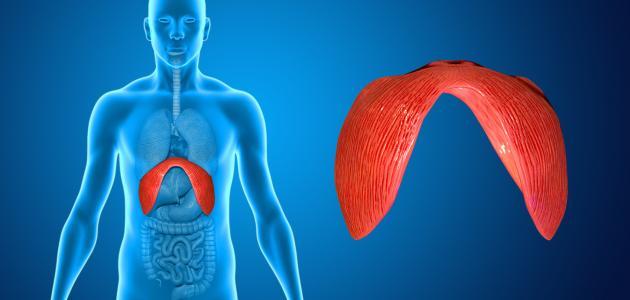

الحجاب الحاجز:

الهيكل العضلي والغشائي الذي يفصل بين تجاويف الصدر والبطن عند الثدييات، كما يُعتبر بمثابة العضلات الرئيسية للتنفس.